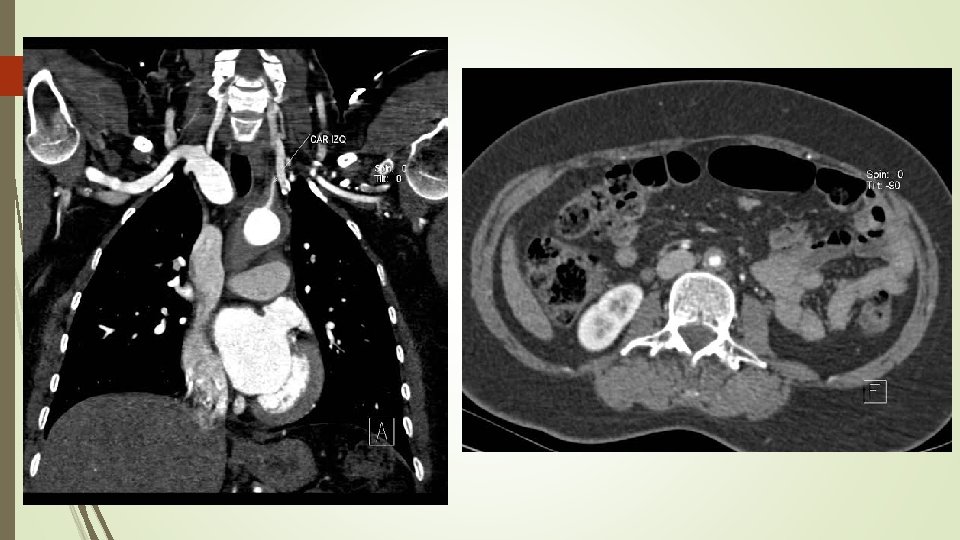

El estudio se informa como Hematoma aórtico agudo intramural tipo A, extendiéndose desde la raíz de aorta hasta la bifurcación de las iliacas primitivas. Ante dicho hallazgos, la paciente es trasladada a la Unidad Coronaria para monitorización y Cirugía Cardiaca. A las 24 horas de ingreso y previa intervención quirúrgica se solicita, angio. TAC de aorta helicoidal sincronizado para una mejor caracterización de la afectación aórtica, con los resultados que se muestran a continuación.

Angio. TAC aorta helicoidal sincronizado - Engrosamiento en forma de semiluna de aorta torácica ascendente y un engrosamiento circunferencial difuso de arco aórtico y aorta torácica descendente, alcanzando la bifurcación ilíaca. - Engrosamiento circunferencial del origen los troncos supraaórticos con estenosis filiforme del origen y primeros centímetros de carótida común izquierda. - Oclusión de arteria subclavia izquierda desde origen de arteria vertebral con repermeabilización de arteria axilar por colaterales. - Estenosis de la aorta abdominal en todo su recorrido siendo filiforme a nivel infrarrenal con diámetro mínimo de 5 mm. - Dilatación post estenótica ilíaca de común derecha. Hallazgos compatibles con Enfermedad Takayasu en fase crónica